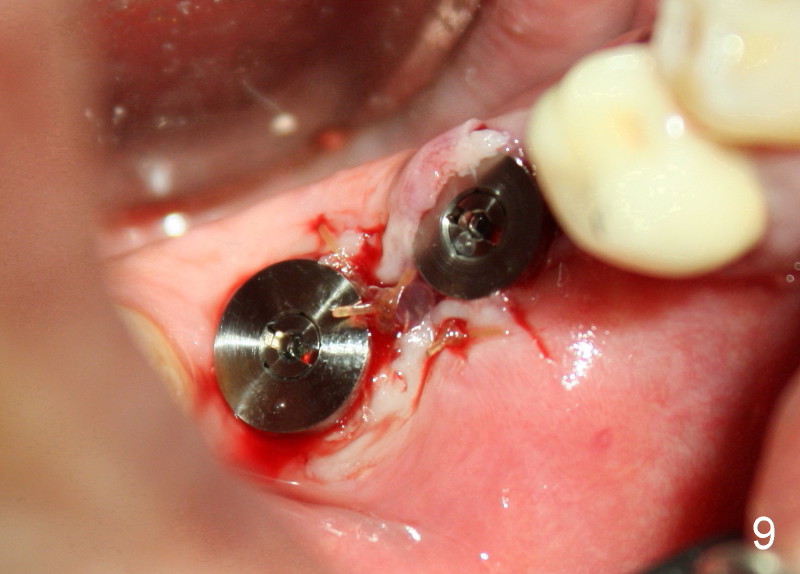

After adjustment, next drills (5x17, and 5x14 mm for #30 and 31) are located more appropriately relative to neighboring teeth (Fig.7) and also in some distance from the inferior alveolar canal (black lines). The septum of #31 is now distal to the drill for #31. Finally 6x17 and 7x14 mm Tatum tapered implants are placed with certain degree of initial stability (Fig.8). Black dashed lines represent the inferior alveolar canal. Fig.9 is taken immediately post-implant placement.